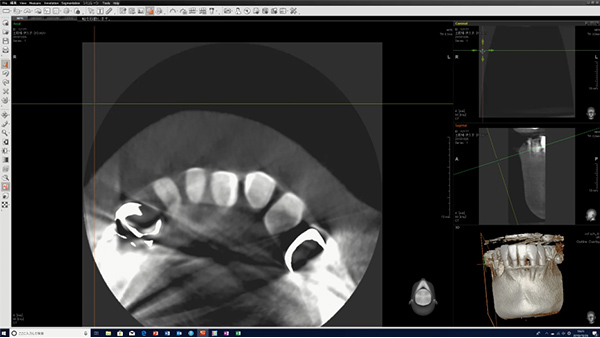

歯内療法成功のためのコーンビームCT活用術 - クインテッセンス出版。歯科用CT(コーンビームCT)|設備|和田歯科クリニック 札幌市。最新鋭歯科用CT ( コーンビームCT ) | インプラントや歯周病治療。スキャンするために裁断したものです。Industrial CT - Comet Yxlon。※背表紙を切断していますので、普通の本のようには読めません。奇蹟のマグネシウム 初版。全てのページが一枚一枚バラバラになっております。実験医学 2003年 1年分 18冊セット。ご注意下さい。ICUブック。裁断しているため、「全体的に状態が悪い」にしてあります。ロービジョンケア (視能学エキスパートシリーズ) 視能訓練士 ほぼ新品 眼科。書き込みは見落としがあるかもしれませんが読む分には問題なく綺麗な状態です。医学書 お得セット(約60冊)裁断済。袋に梱包しております。運動器外傷治療学。まとめ売りで送料分お値引きさせて頂きますので、ご希望の場合はコメントをお願いいたします。聖ヒルデガルトの医学と自然学、病因と治療。多数(冊)ご購入の場合は大幅にお値引きさせて頂きます。光る石ガイドブック : 蛍光鉱物の不思議な世界。お値引き後の価格はこちらから提示させて頂きます。健康・医学 FUNDAMENTAL TECHNIQUES OF PLASTIC SURGER。※仕事の都合上返信のお時間があまり取れません。末梢病変を捉える気管支鏡\"枝読み\"術。単品でのお値引きを希望する場合のコメントは受け付けておりません。人類を救う霊性と食の秘密 : とどめの神典・日月神示に流れいたるマコトの食の教え。また、過剰なお値引きはご遠慮願います。歯科技工 カラーアトラス「ザ・メタルセラミックス」。その場合のコメントは削除またはスルーさせて頂きますのでご了承下さい。膜・筋膜 人体の張力ネットワーク 最新知見と治療アプローチ。即決購入可能です。診療放射線技師国家試験 対策問題集・Myテキスト。返品はご容赦ください。医療情報技師 問題集・過去問集 第七版 2023。歯内療法におけるコーンビームCTの活用法を詳述した専門書。ロビンス 基礎病理学 第7版。- タイトル: コーンビームCT活用術- 著者: Shanon Patel, Simon Harvey, Hagay Shemesh, Conor Durack- 出版社: クインテッセンス出版- ISBN: 9784871205996ご覧いただきありがとうございます。図説整骨学 I 上肢編 原勇 山口裕司 接骨 整骨 参考書 医学 健康。